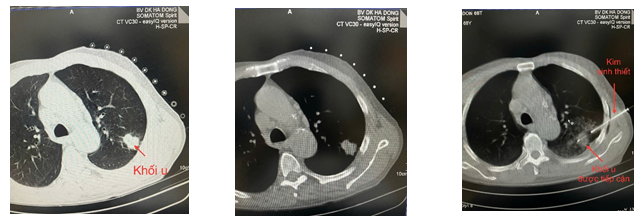

Hình ảnh trên đây, đầu kim sinh thiết đã được định vị và tiếp cận chính xác khối u ở phổi, minh chứng rõ ràng cho độ chính xác của kỹ thuật này.

Sinh thiết phổi là thủ thuật trong đó bác sĩ dùng kim nhỏ chuyên dụng để lấy một phần mô từ khối u hoặc vùng tổn thương nghi ngờ trong phổi, nhằm xác định bản chất của tổn thương.

- Dưới sự hướng dẫn trực tiếp của máy CT, kim sinh thiết được đưa chính xác vào trung tâm khối u.

Tại Khoa Chẩn đoán hình ảnh – Bệnh viện Đa khoa Hà Đông, kỹ thuật này đã được triển khai thường quy với sự hỗ trợ của máy chụp cắt lớp vi tính SOMATOM Spirit – easyIQ version cho hình ảnh rõ nét, độ phân giải cao.